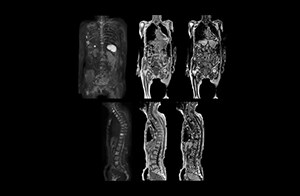

Shorter exam time needed for improving patient acceptance

“In our initial whole body DWI, we scanned from the top of the head to the toe in axial orientation. Because that took a lot of time, it constrained the examination to performing only coronal TSE and the axial whole body DWI scans. So, we had to compromise on clinical information to keep the exam to a reasonable length.” “Fortunately, the Ingenia 1.5T system allowed us to improve our whole body DWI scan and make the exam time more tolerable for patients,” says Mr. Naka.

“Before we had Ingenia, clinical adoption was hindered because the exam length of the whole body DWI protocol on our old system was difficult for many patients to tolerate,” says Takanori Naka, MR technologist.

More clinical information in much shorter exam time

“When we limited the scan coverage to the area from neck to femur, we could fit more clinical information in approximately the same scan time. So, we added coronal mDIXON, sagittal T1-weighted, and sagittal STIR sequences to our examination, instead of performing only axial DWIBS and coronal single-shot TSE scans.” The single shot T2-weighted TSE images are used for morphology and compared to DWIBS images to identify T2 shine-through. Sagittal STIR images are used in patients with inflammation or bone metastasis.

“Once Ingenia was available, our first goal was to shorten the exam time of our scan,” says Mr. Naka. The next goal was to create a protocol that provided more clinical information.

“With coronal DWIBS, we can perform a full whole body exam, including other sequences, within 30 min.”

Coronal DWIBS is faster and improves image quality

“This is considerably faster than the previously used exam with axial whole body DWI, which took more than 45 minutes,” he notes. “A shorter exam is more patient-friendly and allows us to also use it on patients in poor health who would have difficulty tolerating a long exam. Limiting the exam time is also helpful for scheduling, because it fits in a normal single exam timeslot.”

“Switching to coronal DWIBS – rather than axial – further shortens scan time,” says Mr. Naka. “Important is that a dS SENSE factor of 5 shortens exam time while high image quality can be maintained, thanks to Ingenia’s dStream architecture.” He adds that the coronal orientation also avoids artifacts that are specific to combining axial images.

“When we use a coronal DWIBS acquisition, we can perform a full whole body examination, including other required sequences, within 30 minutes,” he says.